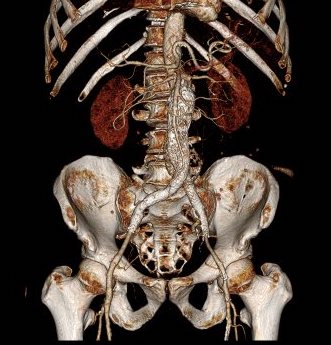

The patient had a 8cm sphere shaped aneurysm arising in the transdiagphragmatic aorta, leaking into the right pleural cavity.

The patient was otherwise a healthy middle aged man with risk factors of smoking and hypertension. The centerline reconstructions showed the thoracic aorta above the aneurysm to be around 20mm in diameter and same below, with the celiac axis and superior mesenteric artery in the potential seal zone of a stent graft. The only plaque seen was around the level of the renal arteries and was focal and calcified. Looking at the list I had made as a comment to the Linked-In post, I realized that I really only had one viable option.

Open repair, usually the most expeditious option, was made challenging by the right hemothorax, making a left thoracotomy hazardous if the lung had to be deflated. Cardiopulmonary bypass would have to be arranged for, and that adds a metabolic hit that greatly raises the stakes. Of the endovascular solutions, the only viable option was TEVAR to exclude the rupture and debranching of the celiac axis and superior mesenteric artery. To those who would advocate for parallel grafts, there was no room in the normal 20mm diameter aorta. And branch systems for rupture are some time in the future. Also, the patient was becoming hypotensive. So the planned operation was first TEVAR to stop the bleeding, and then open surgical debranching. A hybrid repair.